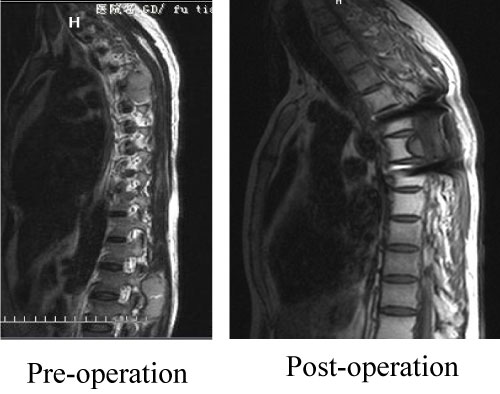

7 years after the right sphenoid ridge meningioma surgery, the patient presented to us again with back pain for 2 months. The magnetic resonance imaging (MRI) and CT (2013) (Figure 8) showed the patient had a surgical scar at the right frontal temporal, a frontal temporal skull defects, and the tenderness and percussion pain on thoracic. The limb muscle strength was level 5, the bilateral limb skin' feeling was normal, the limb muscle tension was not high, and the bilateral Babinski, Brudzinski, and Klinefelter signs were negative. The CT, MRI and CTA examination showed the intracranial meningeal tumor recur again and metasted to vertebra thoracalis and vertebra lumbalis (Figure 9). Three surgery were taken for the recurrence and metastases of the meningeal tumor. Firstly, thoracic tumor resection and thoracic pedicle screw fixation were taken for the thoracic metastasis on general anesthesia (Figure 10) and then the second operation was perform for the resection of the recurrence of meningeal tumor; At last, the lumbar tumor resection and lumbar pedicle screw fixation were taken for the lumbar metastasis on general anesthesia (Figure 11) and the tumor was further diagnosed to be intracranial meningeal hemangiopericytoma.

Figure 10: The MRI test of the first surgery. View Figure 10